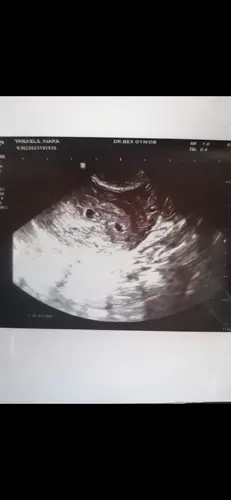

Dankjullie wel dames voor jullie reactie. Werd me gisteren gezegd dat deze grootte wat aan de kleine kant is voor 6 weken. Ik ben onderbehandeling in het zkh vanwege fertiliteittraject. Toevallig belde de verloskundige mij net op, ze willen dat ik bloed ga prikken vandaag. En ze willen opnieuw een echo doen.

Dankjullie wel dames voor jullie reactie. Werd me gisteren gezegd dat deze ...